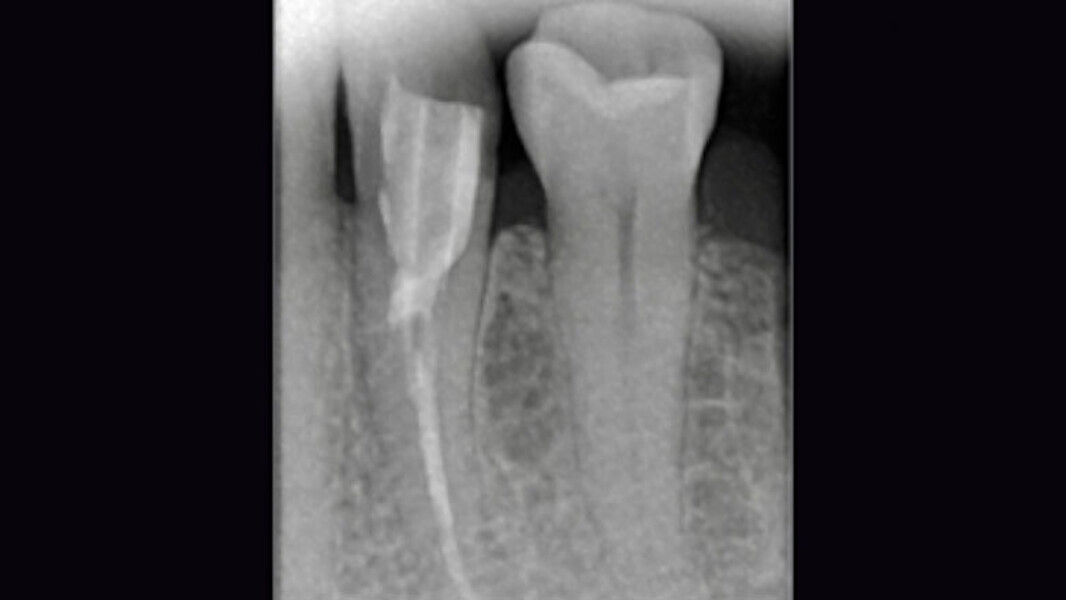

Fig. 1. Situación inicial: el diente 34 estaba fuertemente dañado. La encía se había adentrado en la cavidad.

Fig. 2. Estado tras la revisión, la colocación de la espiga y la reconstrucción.